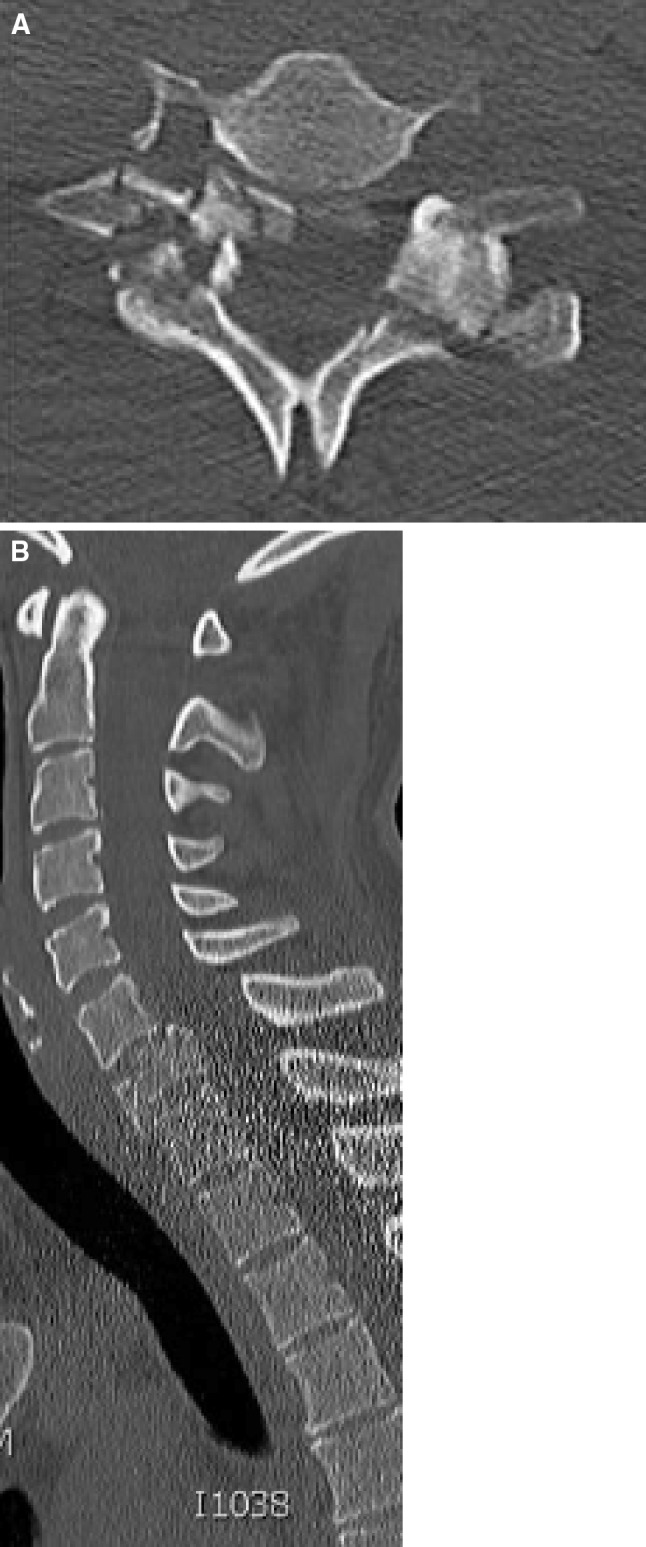

Plain radiographs of the cervical spine (antero-posterior and lateral) as well as a CT scan were performed and revealed a rotational burst fracture of C7 with partial occlusion of the right C7 foramen (Fig. 1). The fracture was classified as C3.1 according to Magerl and Reinhold [1, 2]. Furthermore, a slightly displaced occipital condyle fracture on the right side could be detected (Fig. 2). This fracture was classified as a type III according to Anderson and Montesano [3], and type 2A according to Tuli [4], respectively. In the axial view, a rotational misalignment of 22° to the left of C0/1 against C2 could be observed (Fig. 3).

Fig. 1.

Rotational burst fracture of C7 with right radicular C7 neuropathy due to bony fragment in the C7 foramen

Fig. 2.

Moderate dislocated right occipital condyle fracture